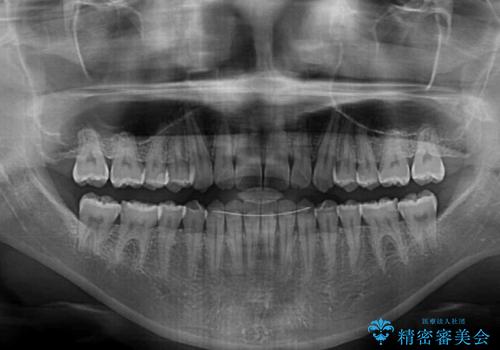

- 後戻りによる上下前歯の隙間を気にして来院された患者様です。

歯列不正はそれほど大きくなかったため、インビザライン・ライトを用いて矯正治療を行うこととしました。

無理のないペースで治療を進め、9ヶ月で終えることができました。